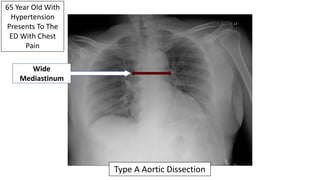

65 Year Old With

Hypertension

Presents To The

ED With Chest

Pain

Wide

Mediastinum

Type A Aortic Dissection

65 Year Old With Hypertension Presents With Chest Pain